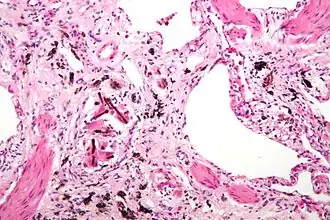

Pneumoconiose of stoflong is een longaandoening die door de inhalatie van stof wordt veroorzaakt.

De stoflongziekte, ook bekend als mijnwerkers-pneumoconiose, ontstaat door langdurige blootstelling aan kolengruis. Dit stof kan niet worden afgebroken of verwijderd door het lichaam, waardoor het zich ophoopt in de longen en ontstekingen en littekens veroorzaakt (bindweefselvermeerdering). Het meest voorkomende symptoom is kortademigheid. Daarnaast kan de ziekte leiden tot emfyseem en hartfalen.